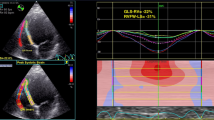

We observed the cardiac events, namely 13 cardiac deaths, 17 LVAD implantations, and 52 hospitalizations for HF during the follow-up (median [interquartile range]: 21 months [8–36]). The Kaplan–Meier survival analysis revealed that patients with different LS patterns had different cardiac event rates (Fig. 2). We performed univariate analyses with variables that were clinically important or different between groups (Table 3). The lower RapLSI, indicating an apical relatively-impaired pattern of the LS, institution, and new-onset HF were associated with a higher cardiac event rate, whereas the GLS, EF, and OMT scores were not in this study. In the multivariable analysis including new-onset HF, institution, OMT scores, and GLS, the association of RapLSI and LS distribution patterns with cardiac events remained significant (Table 4). The rate of LVRR was significantly higher in the apical relatively preserved group (52%) than in other groups (vs. apical relatively-impaired group (8%), p < 0.01; vs. scattered/homogeneously impaired group (25%), p < 0.01). After adjustment for new-onset HF, the association between achieving LVRR and LS distribution patterns remained significant (p < 0.01).

Event-free survival in patients with DCM and reduced EF, based on the RapLSI. The Kaplan–Meier plots of the event-free (A: cardiac death, hospitalization for HF, or LVAD implantation, B: cardiac death or LVAD implantation) survival in patients with HF and reduced EF who are stratified into the apical relatively preserved group (blue), scattered/homogeneously impaired group (green), and apical relatively-impaired group (red), calculated by the RapLSI. DCM, dilated cardiomyopathy; RapLSI, relative apical longitudinal strain index; LVAD, left ventricular assist device; HF, heart failure; and EF, ejection fraction